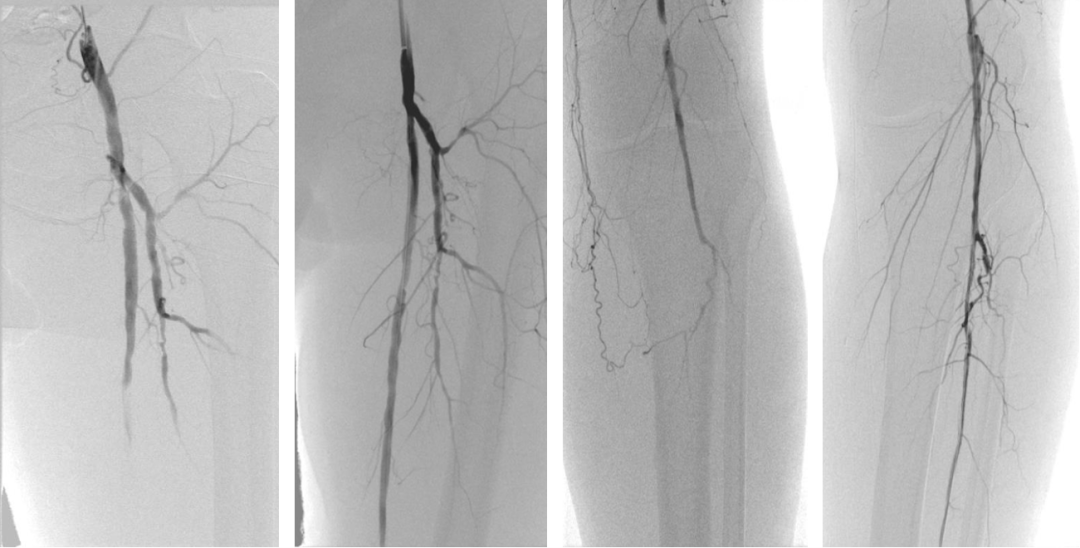

术前

术后

术后12个月和24个月的结果,显示了治疗的效果。

术后12月

术后24月